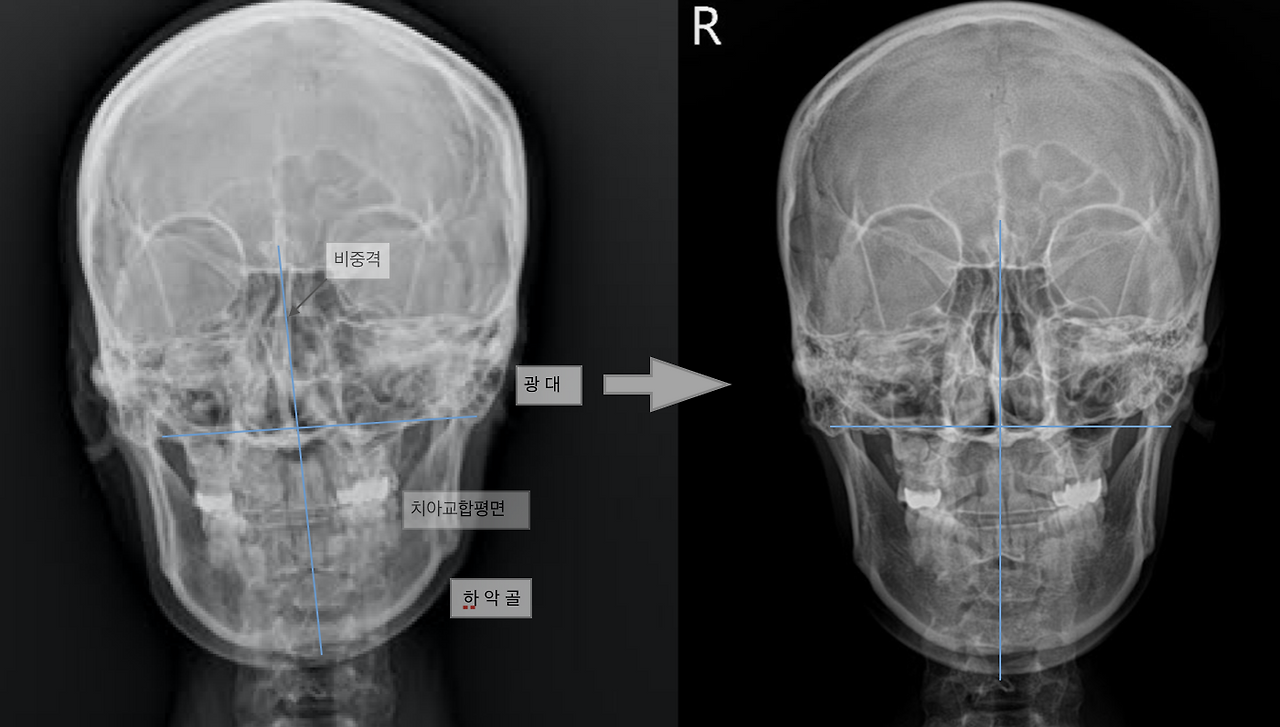

제가 얼굴비대칭을 교정하기 위해 하는 일은 안면골, 특히 턱관절과 경추 그리고 몸의 상대적인 위치관계를 개선시키는 것입니다. 그런데 안면비대칭으로 교정되는 변화는 단순히 피부 영역이나 근육 영역에서만 일어나지 않습니다. 실제로 근육 길이가 조절되면서 안면골 즉 뼈의 위치까지 변화가 나타납니다. 위 환자의 엑스레이 사진인데요. 왼쪽의 치료전 사진은 아래턱과 광대 위치를 포함한 안면골이 오른쪽으로 치우쳐 있는 양상을 볼 수 있습니다. 그런데 교정 치료가 끝나고 나서 찍은 엑스레이 영상에서는 여러 영역의 안면골의 영상에서 변화가 생겼습니다.

1. 교합 평면 기울기 개선

오른쪽으로 내려가 기울어져 있던 교합 평면 ( 오른쪽 어금니 끝~ 왼쪽 어금니 끝을 이은 선)이 수평에 가깝게 회복되었습니다. 오른쪽으로 기울어진 하악골 (아래턱)의 위치가 왼쪽과 비슷한 위치로 이동합니다.

2. 비강내 변화, 호흡개선

비중격의 휜 각도가 완만해졌으며, 동시에 비강 내부의 공기의 순환이 좋아져서 호흡이 편해집니다. ( 엑스레이 영상에서 공기는 까만색으로 보인답니다.)

3. 안면골의 위치 변화

광대뼈 (관골)의 위치가 치료 전에는 오른쪽이 더 올라가 있는데 치료 후 수평에 가까워졌습니다.

4. 안와의 위치 이동

오른쪽으로 치우친 안와의 위치가 중심부로 이동했으며 찌그러진 듯한 안모가 가지런하게 변했습니다.